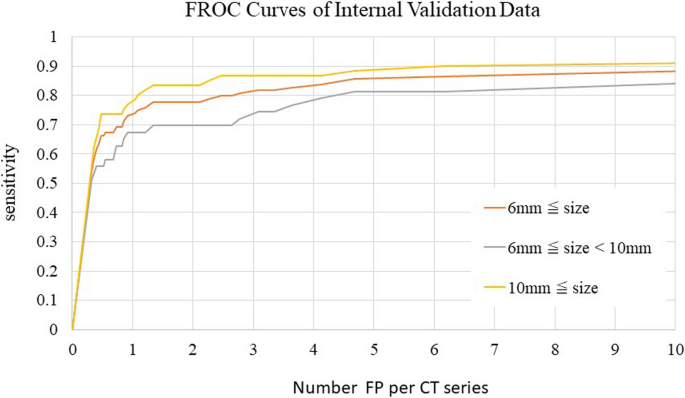

Fig. 6 shows FROC curves for each CT series in the internal validation dataset. The sensitivities for lesions ≥6 mm and lesions ≥10 mm were 0.815 and 0.883, respectively, when the allowed number of FP lesions per image was three. However, the sensitivities for lesions 6 to 10 mm when three or four FP lesions were allowed were low, with values of 0.738 and 0.785, respectively.

Sensitivities of the internal validation dataset based on CT series by FROC analysis. Sensitivity was evaluated in one position.